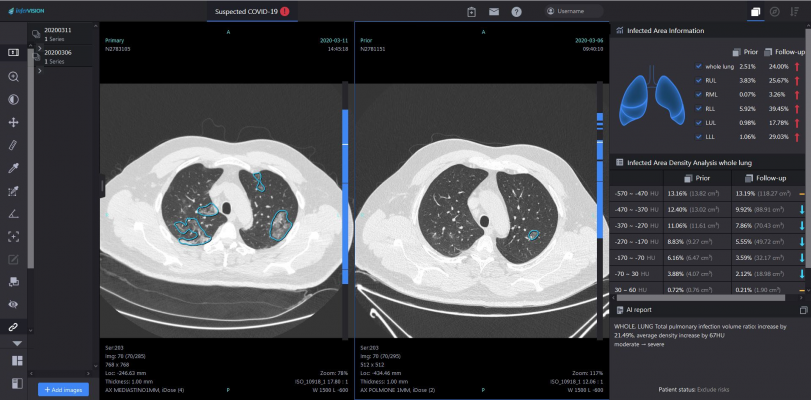

2. Increase confidence in the diagnosis: By automatically measuring and quantifying the density, morphology and volume of lesions, artificial intelligence can provide an immediate and more reliable diagnosis.

3. The development of the disease can be predicted by comparing the scans: The automatic comparison of lesions helps doctors to monitor the patient's condition and development, while at the same time evaluating the effectiveness of treatments more accurately and quickly.

Imaging CT scan: InferRead CT Lung Covid-19 displays the focus of infection in images and calculates volume, density and prognosis. The text of the findings is also generated fully automatically to relieve the physicians.